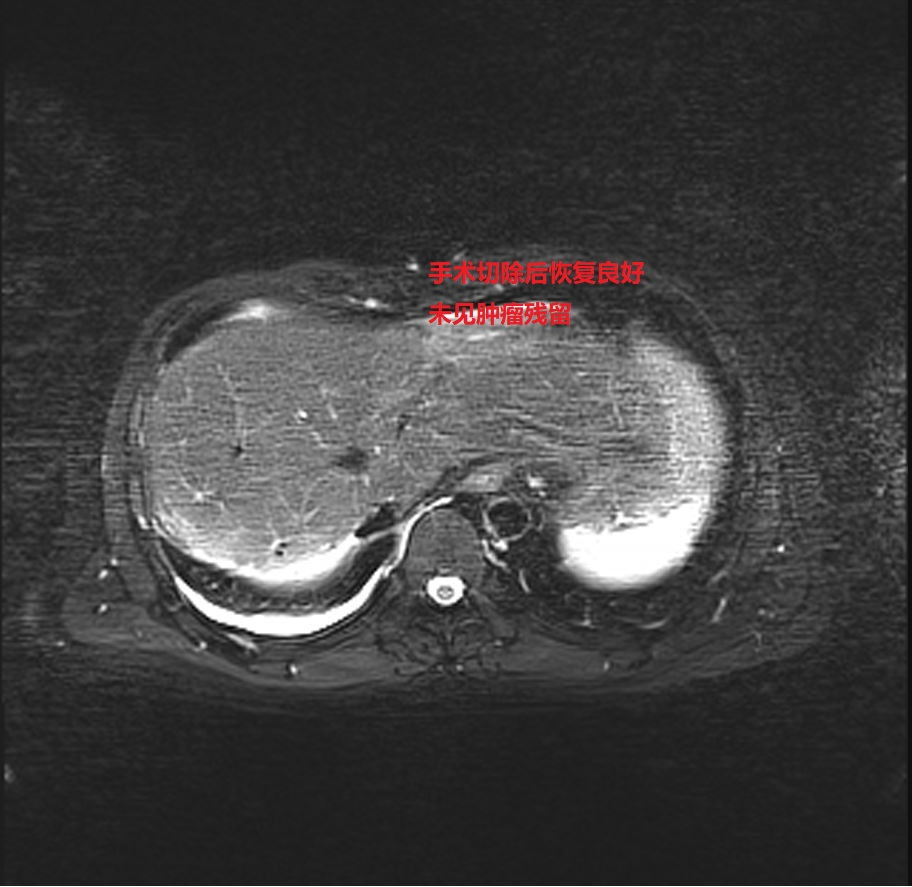

经我院再次肝癌MDT讨论,认为患者肝脏肿瘤降期成功,可以进行手术切除。2024年9月27日,肿瘤科团队为患者成功行了“肝癌根治性切除术”,手术顺利,肿瘤完整切除,患者获得新生。目前已康复出院。